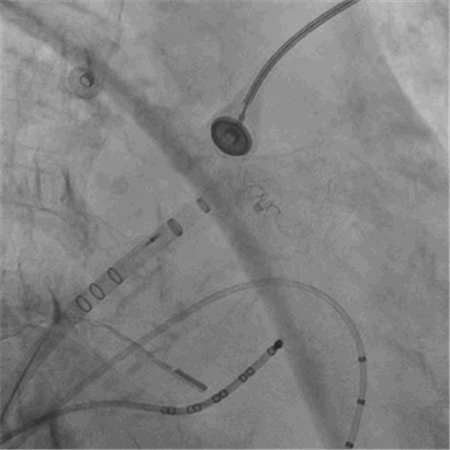

左心耳封堵后造影